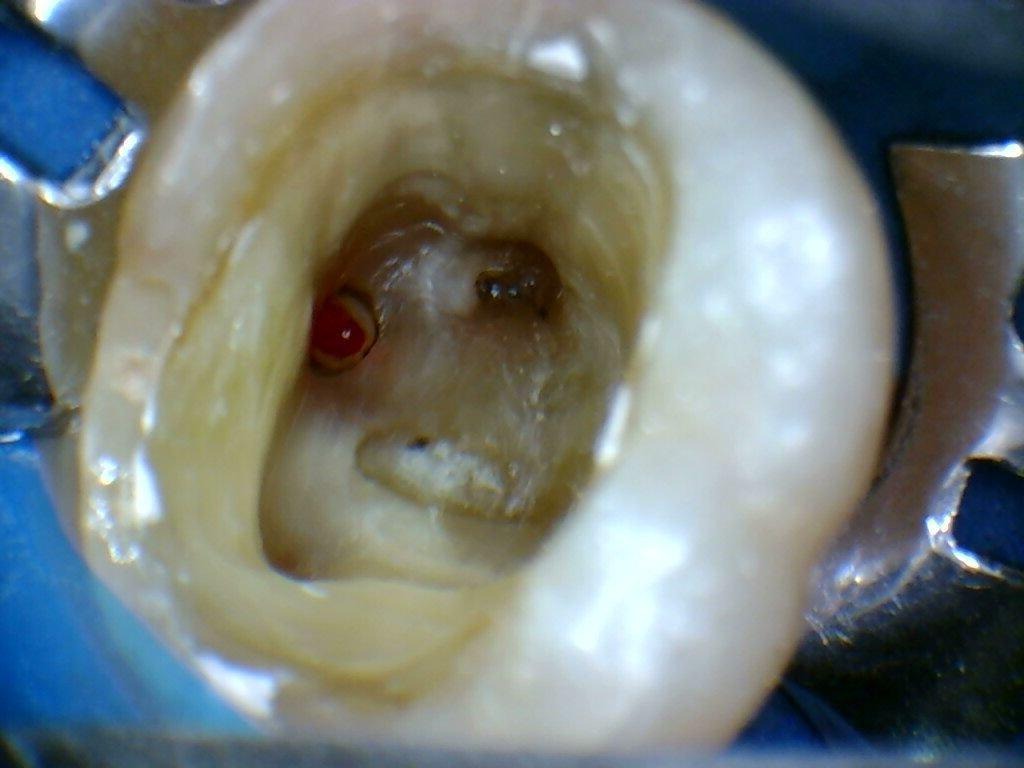

A localização dos condutos radiculares foi realizada com o auxílio de equipamento ultrassônico, sob supervisão de profissional especializado, permitindo precisão e segurança durante o procedimento. Após a localização, aplicou-se uma barreira gengival apenas na área da perfuração, permitindo o uso controlado de irrigantes potencialmente irritantes sem comprometer a região, o que possibilitou a continuidade do tratamento de forma segura.

Tamponamento da perfuração com barreira gengival